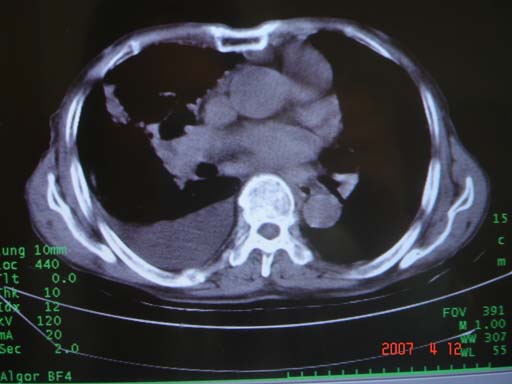

帮我 看看。男77岁咳嗽咯血2月发热2周!病人一般情况可 口痰为鲜红,有点象洗肉水(我看见他吐的痰了)

优先考虑右上肺干酪性肺炎并同侧中叶播散、胸腔积液。分析:右膈肌未见升高、纵隔未见明显右移,胸部各组淋巴结未见可疑肿大,中叶可见支气管铸形,肺野、肺门未见可确定肿块。

年龄偏大,应考虑右肺中央型肺癌并阻塞性肺炎 阻塞性肺不张,胸腔积液

考虑右侧中心型肺癌伴中叶肺不张,右侧 胸腔积液

右肺上叶中心型肺癌并上叶阻塞性肺炎,中叶炎症,右侧胸腔积液

右肺上叶后段支气管中断,首先考虑中央型肺癌并右肺不张及纵隔淋巴结转移,右侧胸腔积液。

右肺中心型肺癌可见支气管呈鼠尾状

有点象洗肉水的痰,其来源应当是实变引起的血细胞渗出导致,可见支气管气象,实变区有虫蚀状空洞,有明显胸腔积液,未见明显肺门区肿块影,考虑继发型肺结核,干酪性肺炎

右肺上叶实变,实变范围如此之大,如果用肺癌解释的化,应该是比较大的支气管开口发生完全阻塞,但观察上叶前后段支气管还是比较通畅,所以应考虑感染性病变,大叶性肺炎可能,建议抗炎治疗后复查。

考虑右中上叶大叶性肺炎,右侧胸水。抗炎治疗后复查。